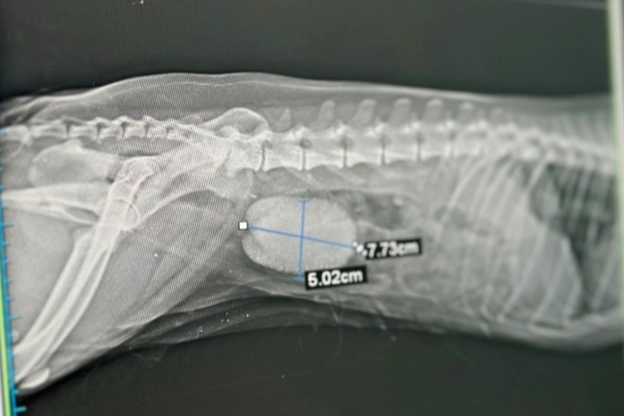

Diyarbakır’da 10 yaşındaki köpeği Fındık’ın sancılı ve kanlı idrar yaptığını fark eden sahibi, köpeğini hayvan hastanesine götürdü. Röntgeni çekilen Fındık’ın idrar kesesinde, eni 8, boyu 5 santim olan iri taş olduğu belirlendi. Fındık’ın idrar kesesini dolduran taş, operasyon sonucu çıkartıldı. Operasyon hakkında bilgi veren Dicle Üniversitesi Veteriner Fakültesi Cerrahi Anabilim Dalı Öğretim Üyesi ve Hayvan Hastanesi Başhekimi Prof. Dr. Sadık Yayla, bu boyutta bir taşa nadiren karşılaştıklarını söyledi.

Taşın neredeyse kesenin tamamını doldurduğunu belirten Prof. Dr. Yayla, “Ameliyat için hastanemize gelen fındık isimli köpeğin idrar kesesinde taşı vardı. İdrar kesesinde taş olduğu bulgularıyla zaman zaman karşılaşıyoruz ama bu boyutta taş nadir karşılaşılan bir durum. Yaklaşık 8 ve 5 santimetre ebatlarında bir taşı vardı. Hayvanın kendisi de yaklaşık 10 kilogram. Neredeyse kesenin tamamını bu taş doldurmuştu” dedi.

Fındık’ın sağlık durumunun iyi olduğunu dile getiren Yayla, “Fındık isimli köpeğin şikayeti sancılı ve kanamalı idrardı. O yüzden ameliyat önerdik. Tedavisi de ancak ameliyatla mümkündü. Ameliyatımız çok güzel geçti. Taşı da çıkardık. Şu an hayvanın durumu iyi. Taburcu işlemlerini başlatacağız. Fındık, 10 yaşında bir köpekti. Hasta sahibi 3 yıl önce taşı fark etmiş. Ama anesteziden kaynaklı geciktirmiş. Dolayısıyla taş keseyi tamamen dolduracak kadar büyümüştü” ifadelerine yer verdi.